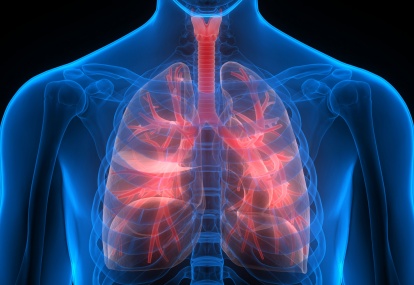

An 18-year-old man is referred to the respiratory clinic for review of possible asthma

The patient reports receiving a clinical diagnosis of ‘mild asthma’ as a child but has never had formal pulmonary function tests, and has been on PRN salbutamol for years.